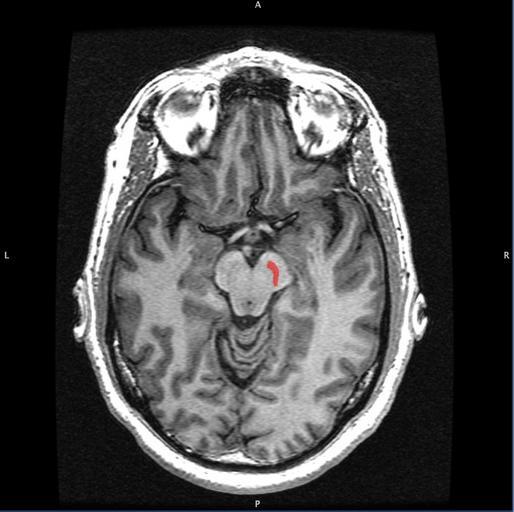

| View Original: | Substantia Nigra.jpg (849x846) | |||

| Keywords: Substantia Nigra.jpg en Horizontal MRI T1 weighted slice with highlighting indicating location of the substantia nigra own Geoff B Hall 2011-09-08 Cc-zero Magnetic resonance imaging of the brain Substantia nigra | ||||